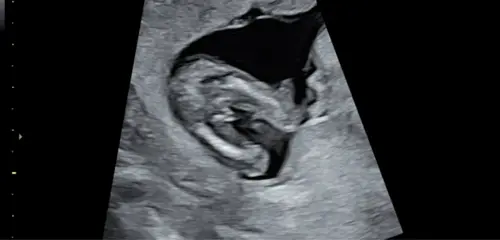

Oe ik denk ook een zoontje , zou natuurlijk ook de navelstreng kunnen zijn maar denk jongetje

Ja dit is toch overduidelijk een jongen? Heb zelf een jongen en nu weer zwanger van een jongen. Anders even googlen hoe een potty shot van een meisje eruit ziet? Dan kun je zien dat dat echt heel anders is.

Ik zeg toch dat ik het er anders uit vind zien dan bij mijn eerste zoontje.

Dit was 13+4 doen alsnog een echo want dit was de medische. Maar duidelijk jongen